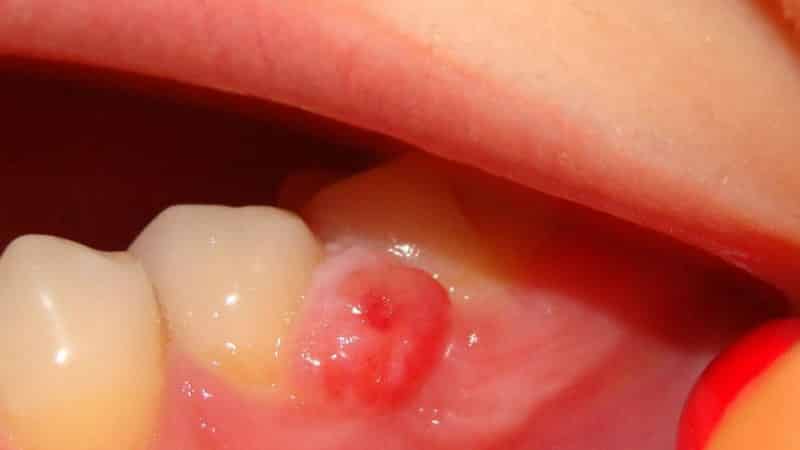

Гнойник на десне у ребенка является следствием локального воспаления тканей десны и корня зуба. Он проявляется в виде круглого образования различного размера и может сопровождаться периодическими болями.

Воспалительный процесс часто начинается с формирования межзубного и десневого кармана, где скапливаются вредные бактерии. Неправильный уход за полостью рта или его отсутствие создают идеальные условия для развития инфекций, а также сниженный иммунитет у ребенка играет важную роль в образовании гнойника. Гнойник может возникнуть также из-за кисты на десне у ребенка, фото которой можно увидеть ниже.

Не каждый родитель сможет самостоятельно отличить гнойник от обычного образования, поэтому важно обратиться к врачу для подтверждения диагноза. При наличии кариеса гнойное образование может быть связано с пародонтитом. Различные травмы в области рта, которые повреждают мягкие ткани, могут способствовать образованию гнойного мешка на десне у ребенка. Важно обращать внимание на жалобы и следить за состоянием ротовой полости, так как опухоль может развиваться постепенно, начиная с безобидной припухлости. Если вы заметили белую точку в центре припухшей области десны, это может указывать на формирование гнойничка. Дети часто пробуют на прочность свои зубы, беря в рот различные предметы, поэтому необходимо внимательно следить за появлением ранок. Образования могут сопровождаться острыми или ноющими болями, повышением температуры. Хотя гнойник может лопнуть сам по себе, не стоит затягивать с лечением. В дальнейшем может образоваться свищ на десне, и как с ним справиться, должен подсказать специалист. В большинстве случаев очаг инфекции остается, что означает, что любое раздражение может привести к повторному образованию гноя на десне.